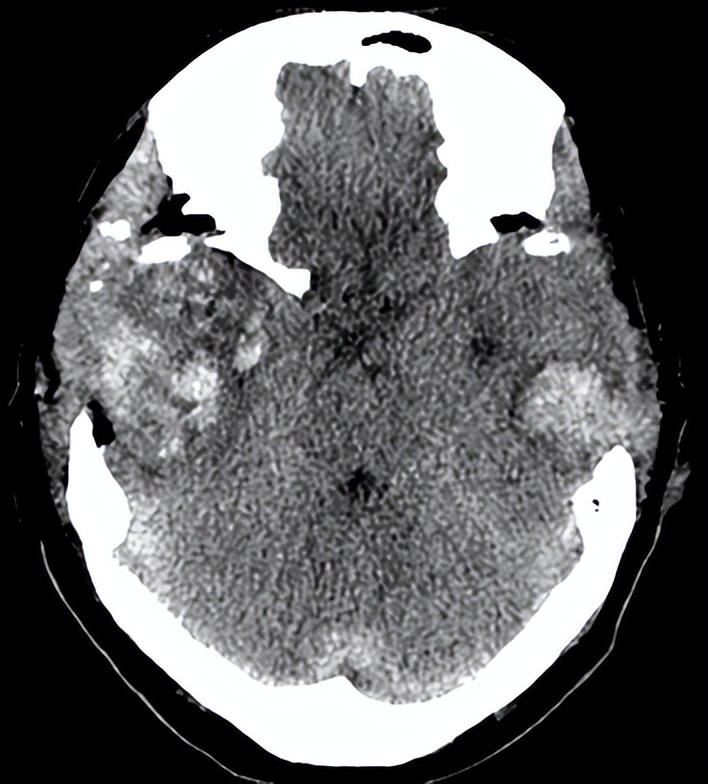

术后第三天,复查头颅CT(见下图)提示患者 脑水肿较前明显, 中线较前移位明显。目前正处在脑水肿高峰期,如果中线移位继续加重时,有必要 再次开颅 进行血肿清除。 病情危重 ,院方向患者家属交待病情,家属中有一位懂医的,都表示理解。

06-10(术后第三天复查头CT)

我被邀请查看了该患者。我先看了6月10日的头颅CT,又亲自检查了患者。

当时患者仍呈 昏迷状态 ,血压148/70mmHg,自主呼吸不规则,需有创呼吸机辅助通气,痰多,有明显痰鸣音。双侧瞳孔等大,约1.5mm,对光反射消失。脑干反射明显减弱。疼痛刺激右下肢回缩反应,左下肢无肢体回缩,双侧巴氏征阳性。

最近一次头颅CT,脑水肿明显,中线移位,双侧脑组织有继发性血肿。